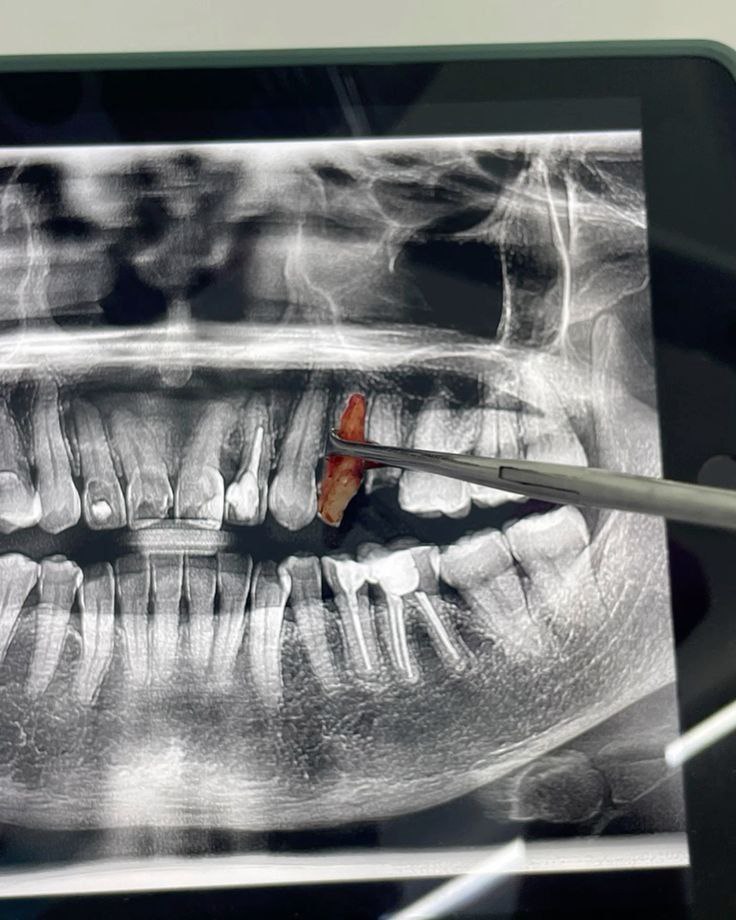

کشیدن دندان: نکات و مراقبت‌های ضروری برای بهبودی سریع

جراحی ریشه شکسته

کشیدن دندان عقل و سایر دندان ها